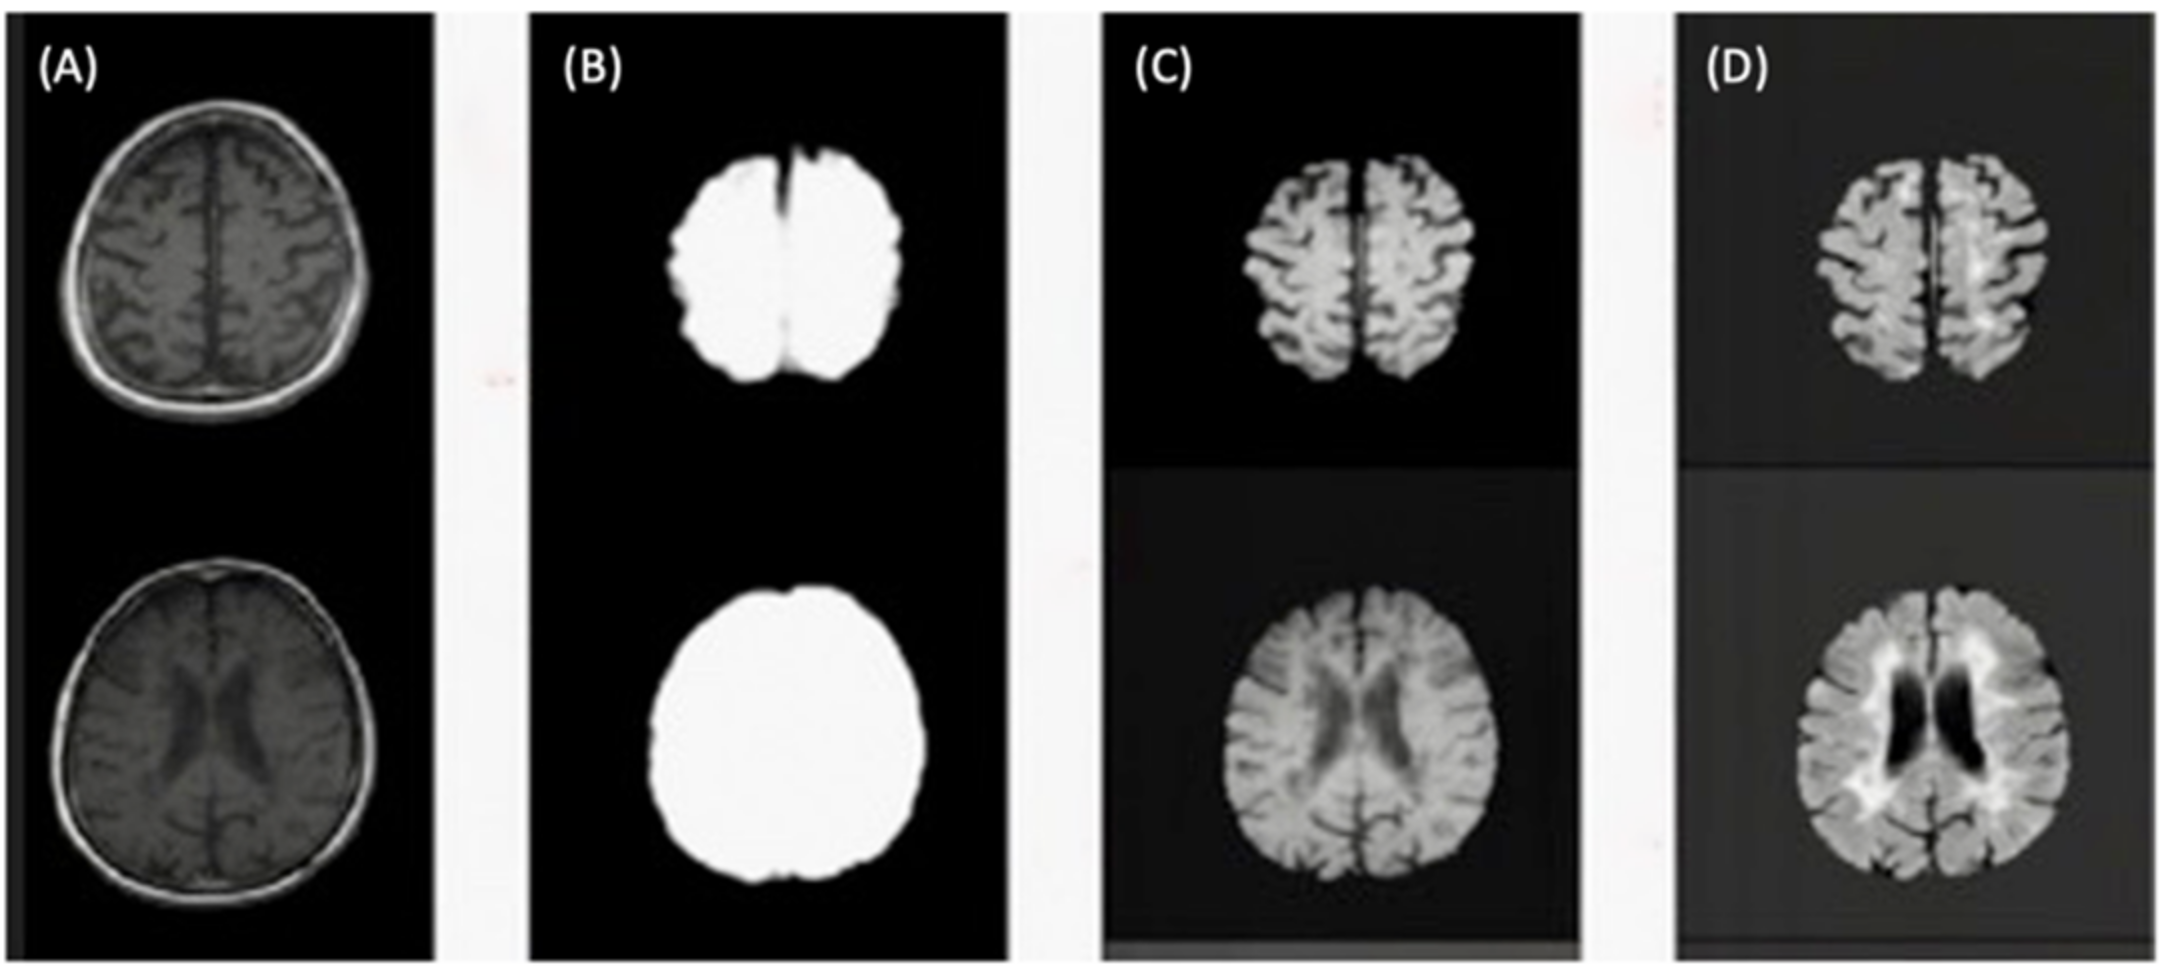

Figure 5 illustrates the skull-stripping process using the U-Net architecture for brain extraction described in step five.

Figure 5.

(A) Slices from original T1-w image. (B) Brain mask through skull-stripping using CNN. (C) Brain extraction in T1-w. (D) Brain extraction in FLAIR image.